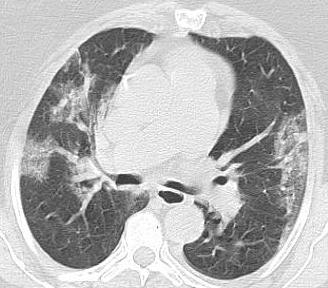

İnönü Üniversitesi Tıp Fakültesi Biyoistatistik ve Tıp Bilişimi Anabilim Dalı tarafından tasarlanan açık kaynak erişimli yapay zekâ tabanlı yazılım prototiplemesi ile covid-19 tanısında hekimlere klinik destek sağlayabilecek bir modelin geliştirilmesi hedeflenmektedir.

Toraks (göğüs) Bilgisayarlı Tomografi (BT)

cihazlarından alınan görüntüler kullanılarak derin öğrenme ve görüntü işleme tabanlı bir model oluşturulmuştur. Tasarlanan bu eğitilmiş model sayesinde covid-19 sınıflandırılması geliştirilen web tabanlı yazılım prototiplemesi ile yapılabilmektedir.